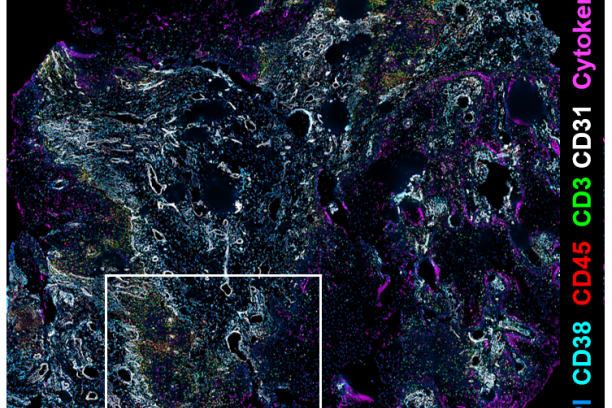

We are so excited to offer the PhenoCycler (formerly CODEX) as a new core service through the Innovative Translational Shared Resource at the Vanderbilt Ingram Cancer Center! The CODEX is a highly multiplexed immunofluorescence system that provides spatial characterization of the tissue microenvironment at the single cell level and uses single step staining to preserve tissue integrity and an automated process of imaging biomarkers using the PhenoCycler instrument and Keyence BZ-X 810 microscope.